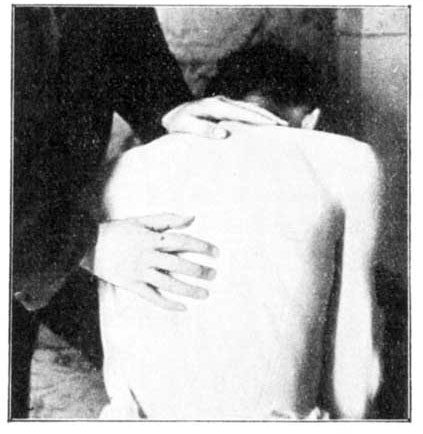

Prepare a bed (long enough for the patient to lie at full length upon his back), with a large thick sheet folded on the lower part of it. Spread over this sheet a blanket wrung out of hot water, so as to be both moist (but not wet) and warm (see Fomentation). See that the blanket is not so hot as to burn the patient and add to his pain. It must be tested with the back of the hand, and be just as warm as this can well bear. On this let the patient lie down, and wrap him up tightly in it from the feet up to above the haunches. Have two or three towels folded so as to be about six inches broad, and the length of that part of the patient's spine above the hot blanket. Wring these out of cold water. Place one over the spine, so as to lie close along it; on this, place a dry towel to keep the damp from the bed, and let the patient lie down on his back, so as to bring the cold towel in close contact with the spine. When this towel becomes warm, another cold one must be put in its place. After about half an hour's pack and eight changes of the cold towel, the pain in the chest should be subdued for the time. If the cold towel does not heat in five minutes, the patient's vitality is low, and a hot cloth should be placed along the spine, and renewed several times, and then another cold one; but as a rule this will not be required. When taken out of the pack, let the skin be washed with soap (see) and warm water; then a slight sponge of nearly cold water, and a gentle rubbing with olive or almond oil. Rub the back first, and gently "shampoo" all the muscles; that is, knead and move the muscles under the skin so as to make them rub over one another.

Ankle Swelling.—When long continued in connection with disease or accident, this sometimes leads to a partial withering of the limb up to its very root. In such a case it is best to deal first with the roots of those nerves which supply the limb, which are, in the case of the legs, in the lower part of the back. It is important to apply light pressure to these roots by gently squeezing the muscles of the lower back. This raises a feeling of gentle heat, which slowly passes down the limbs even to the toes. Then the gentle pressure and squeezing must be carried all down the limb, avoiding any degree of pain, until all its muscles have had their share. While progressing down the limb with his rubbing, let the rubber be careful that the individual strokes of his hands be upwards, towards the hip. The blood will thus be propelled towards the heart, while the stimulus of rubbing is conveyed along the nerve trunks towards the foot. The squeezing should be done with a grasping movement of the hands, the limb being held encircled in both hands, thumbs upwards. Warm olive oil is used in this squeezing, and also, if the skin be hard and dry, soap lather (see Lather).

Treatment may also be given for lack of assimilative power. The back, especially on either side of the spine, is rubbed with gentle pressure and hot olive oil. This pressure is so applied that a genial heat arises along the whole spinal column. This done twice a day, for half-an-hour at a time, and continued for several weeks, will markedly restore assimilative power. Cases which have been perfectly helpless for eight and even ten years are cured by this simple method, sufficiently and carefully followed.

An attack of this may often be relieved by rubbing, with the points of the fingers chiefly, gently yet firmly up and down each side of the spine, close to the bone. Even rubbing above the clothing will frequently relieve. The roots of the nerves supplying power to the breathing muscles lie just on each side of the spine, and this kind of rubbing stimulates these roots. It is not rubbing of the skin or backbone which is wanted, but such gentle treatment of the nerve roots on either side of the bone as makes them glow with genial warmth. This rubbing is of course better done on the surface of the skin. See that the patient is warm, then dip the fingers in cold water, and rub as directed. When the water makes the patient feel chilly or he tires of it, use fresh olive oil, warmed if necessary. Avoid all alcoholic drinks, which simply rob the nerves of the very power needed for cure. Temporary relief may be given by such drinks, but it is at the expense of lowered life and reduced chances of recovery.

The best manner of applying cold to the spine is described in article on Angina Pectoris. Towels are folded as there directed. The moist one (well wrung out) is placed next the spine, either over the part desired or the whole spine. The dry one is placed over this, and the patient lies down on his back on the top of them; or, if he cannot lie, as sometimes happens, the towels are gently pressed with the hand against the spine until sufficient cooling has resulted. The patient should never be made to shiver. If he feels chilly, hot fomentations to the feet and legs, as described in article on Angina Pectoris, may be applied.